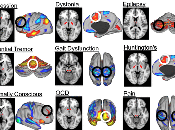

Brain Resting State Network Stimulation for Psychiatric and Neurological Diseases

Fox et al. do a survey of therapy using either invasive approaches, such as deep brain stimulation (DBS), or noninvasive approaches, such as transcranial... Read more